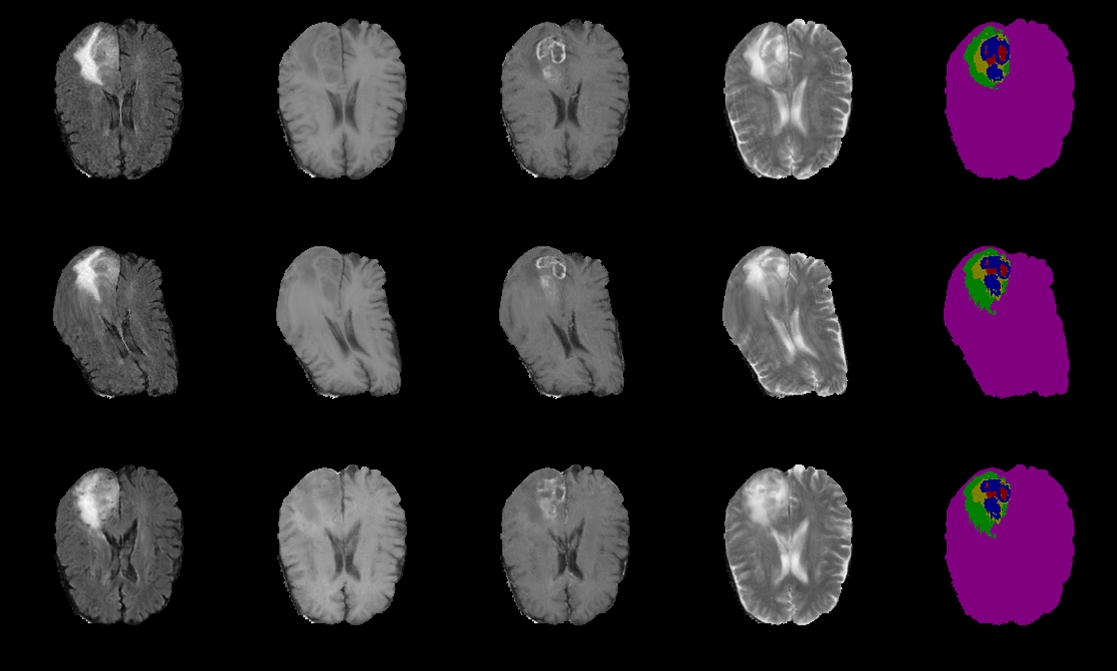

Refer to caption

Figure 2: Example of a synthetic high-grade glioma tumor. Left to right: FLAIR, T1, T1c, T2, expert delineation (Ground truth) and semantic label map (Red: necrosis, Green: edema, Yellow: non-enhancing tumor, Blue: enhancing tumor).

Instead, we propose applying the elastic deformation to the label map. After that, we create a set of semantic labels from the deformed label maps. Specifically, we label 111 to 555 for necrosis, edema, non-enhancing tumor, enhancing tumor, non-tumor brain regions and 00 for everything else in the semantic labels. We use the semantic labels instead of the label maps as input for our proposed CB-GANs. By providing the information of the contour of the brain to the generator, it further diversifies the synthetic brain MR image with different shapes and prevents model collapse, i.e., prevents the model from generating a set of realistic MR images with the identical shape and context of the brain. Figure 2 and 3 show the example of the synthetic image generated by CB-GANs with corresponding semantic label map.